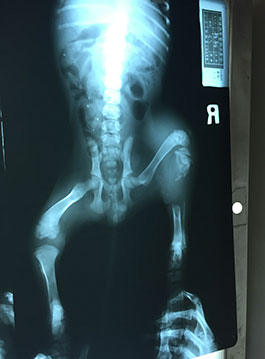

小濱濱是一個無家可歸且右後腳斷掉的幼犬,被一位小姐撿到帶來醫院治療,原本小姐是想去海邊附近尋找被遺棄的小貓,結果卻看見做一半愛心的情侶將小濱濱放置高高的河堤上,當時小姐詢問他們為何要把小濱濱丟棄在那,情侶說明他們是在馬路上看到小濱濱腳斷了,很可憐,帶牠去醫院檢查,但付不出醫藥費,就把牠遺棄放置那裏,緊接著就離開了,留下徬徨無措的小濱濱,小姐不忍心小濱濱獨自待在又高又偏僻的地方受苦,就帶來與協會合作的醫院進行治療。

醫師看了小濱濱的狀況也照了X光,發現小濱濱的骨頭已被細菌吞噬掉了,不過醫師並沒有放棄牠,前前後後進行了三次手術,小濱濱意志堅強,不僅撐過每個療程,並且在復健後能正常行走;復原後的小濱濱,每天都很好動,跑來跑去呢!現在的小濱濱已經找到牠幸福的歸屬囉。